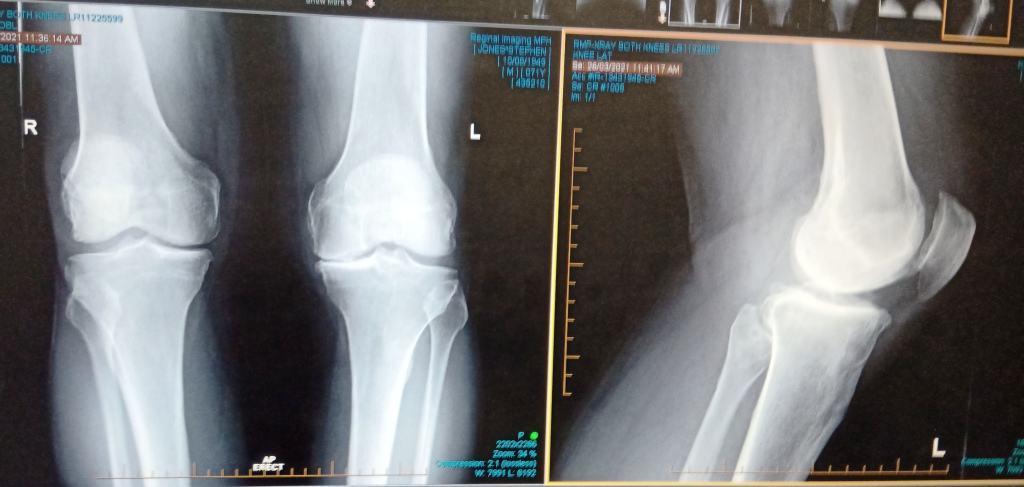

The (top) X-ray below shows how the cartilage on the inside of my left knee is completely gone so that the two bones have been grinding together (painfully) for some time now. The right knee is not much better. I could have just had a half knee replacement which is a little less traumatic, but I would still have had to have the whole knee replaced down the track and it is (procedurally) a lot better to just go for the full replacement as each successive operation becomes more difficult and makes a good outcome that much harder. I have several experts’ advice on this.

The X-ray shows lots of nasty arthritis too particularly under the patella (knee cap).